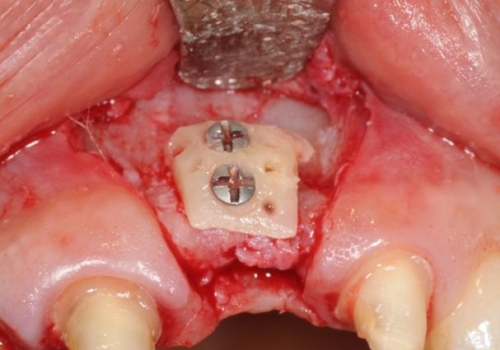

Bərpa texnikasının müəyyən edilməsi, sümüyün hansı bölgədə, hansı miqdarda itirilmiş olmasına bağlı olaraq müəyyənləşdirilir. Bərpa üçün tətbiq edilən sümük materialları pasiyentin öz donor bölgələrindən xüsusi metodlarla qazanılmış sümüklər, o cümlədən digər fərdlərdən alınmış və xüsusi qaydada hazırlanmış materiallar, heyvan mənşəli sümükəvəzləyici materiallar və sintetik materiallar olaraq ayrılır.

Bərpa zamanı yerinə görə bu materiallar ya ayrı-ayrılıqda, ya da kombinə olunmuş şəkildə tətbiq oluna bilir. Gündəlik təcrübədə həmçinin pasiyentdən götürülmüş qan nümunələrindən alınmış yüksək bərpaedici xassəyə malik materiallar (PRF) da uğurla tətbiq olunur. Sümükartırma metodlarının tətbiqi sayəsində, çənədə implantların yerləşdirilməsi üçün yetərsiz sümük həcmi olan bölgələrdə sümük miqdarı yetərli duruma gətirilir, uyğun boy və diametrə uyğun implantlar uğurla tətbiq olunur.